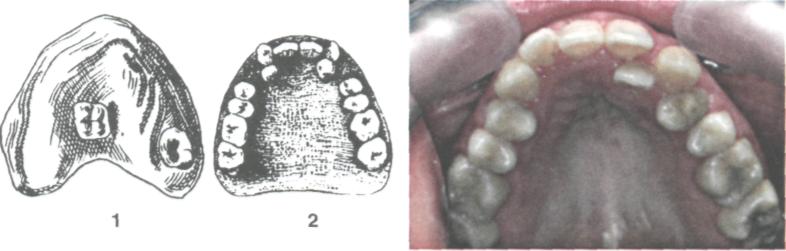

✔️ Сверхкомплектные зубы

Удаление сверхкомплектного зуба

Удаление сверхкомплектного зуба